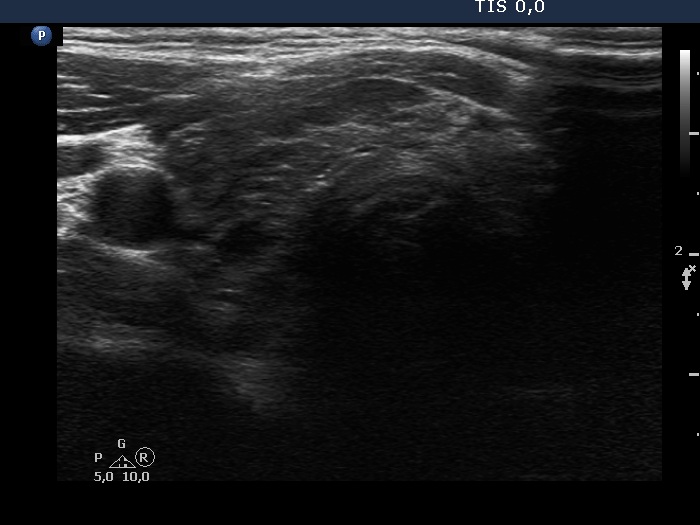

Ultrasound. The thyroid has echonormal and hypoechoic areas. The echogenicity index was greater than 50%. There was a relatively larger echonormal areas in the central-dorsal part of the left lobe. This was less influenced by the underlying thyroiditis. Nevertheless, neither this nor other areas in the thyroid corresponded to true nodules. the so-called honeycombing pattern, i.e., there were numerous small hypoechogenic areas within an echonormal background. The largest hypoechogenic area was misinterpreted as a nodule on previous ultrasound examination. This field was simply the largest of the similarly hypoechogenic parts of the thyroid. Considering the body mass, the thyroid was not enlarged.

It is worth analyzing the presentation of the left lobe. The pattern demonstrates how the thyroiditis infiltrates the normal parenchyma. In this case, the interpretation of echonormal areas should not be a major concern, these are not true nodules.